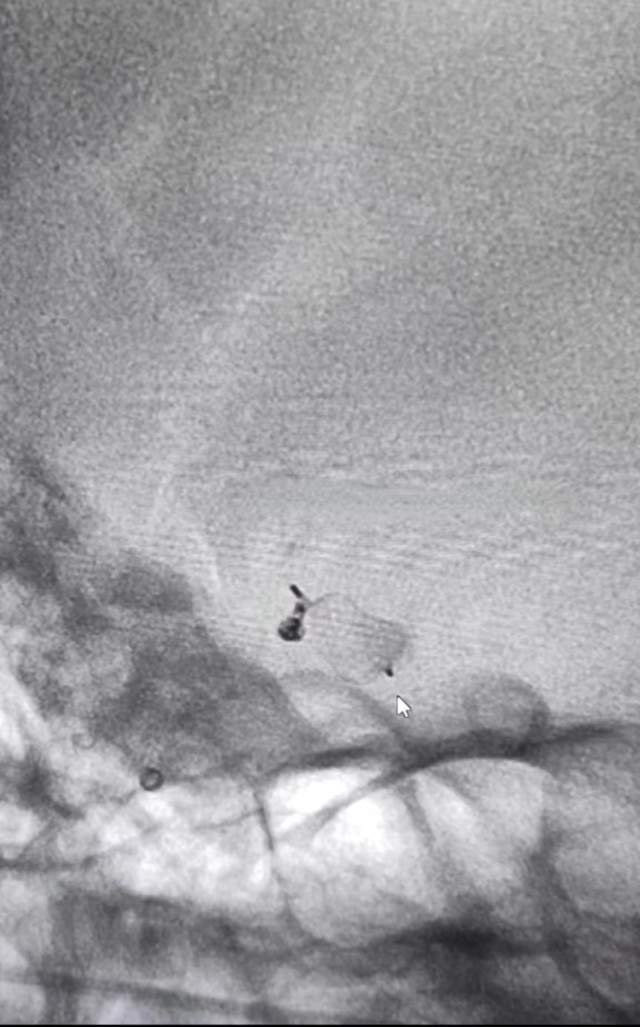

术前图片

全脑血管造影检查显示,此患者的动脉瘤位于前交通动脉,瘤体大小约5.58*5.57*7.74(mm),瘤颈口宽约4.82mm,瘤颈部见一突起小子囊。如行常规的动脉瘤栓塞手术,需行颅内支架辅助栓塞,术后长期双抗的使用引发出血的风险极高。